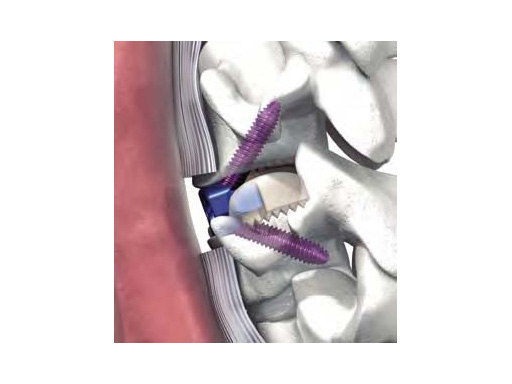

Zero-P acts as stand-alone implant for use in cervical interbody fusions. Its design combines the functionality of a cervical interbody spacer and the benefits of an anterior cervical plate.

The name Zero-P refers to the zero anterior profile or the fact that it is contained in the excised disc space and does not protrude past the anterior wall of the vertebral body as do anterior cervical plates. Since the implant has zero profile, it may reduce the occurrence of adjacent level ossification and postoperative dysphagia.

After the removal of the cervical disc, trial spacers are used to determine implant height, shape, and footprint size. After the correct trial spacer is fitted, the corresponding Zero-P implant is inserted using the aiming device. Because plate and spacer are preassembled, the plate is automatically aligned upon implant insertion. This avoids the process of aligning and realigning an anterior cervical plate.

To prepare the screw holes, instruments for awling and drilling are available. For anatomically challenging situations like patients with short necks, angled instruments are available. The Zero-P screws have a one-step locking conical head, which locks the screw to the plate by simply inserting and tightening the screw.